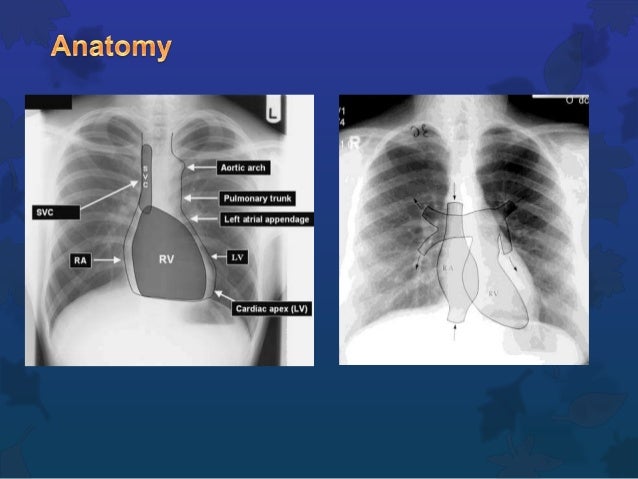

Chest X Ray Review.

Chest X-ray Anatomy

cxr scapula radiology diaphragm hemi